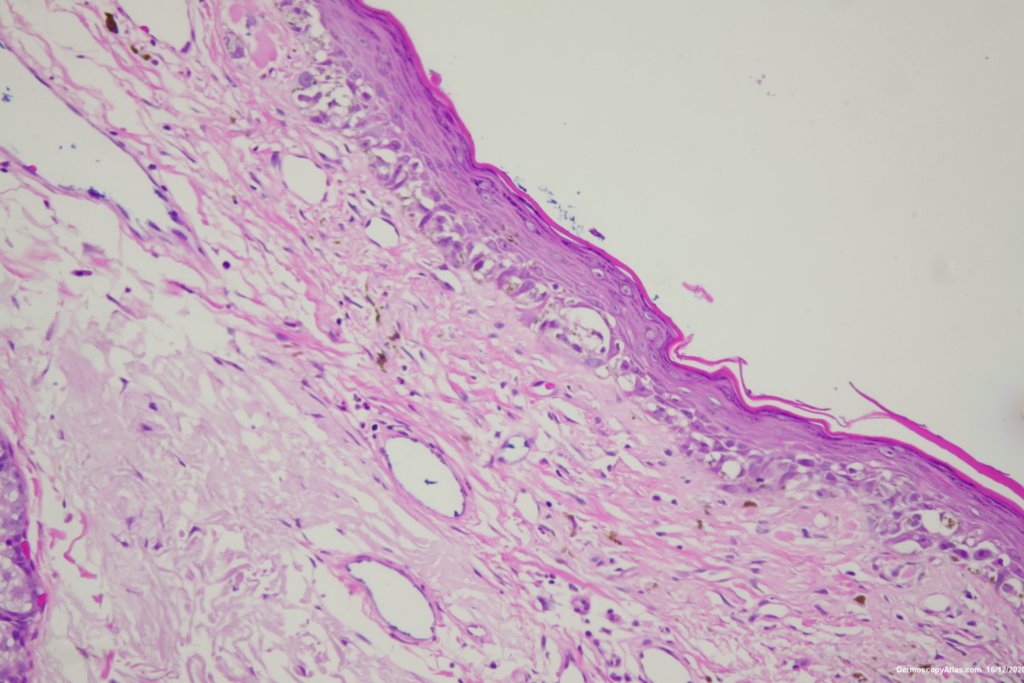

Diagnosis: Lentigo Maligna

Elderly male with no past history of melanoma developed these two lesions over a year or so. The lentigo maligna was easy to diagnose on the clinical and dermatoscopy but the nodule was more difficult. Was it an amelanotic melanoma, BCC or SCC were the initial thoughts. Histology showed a well differentiated sebaceous carcinoma. The two lesions were excised in the same specimen with 5 mm margins. Studies failed to show the mutation for the Muir Torre syndrome which can be seen with sebaceous carcinoma.